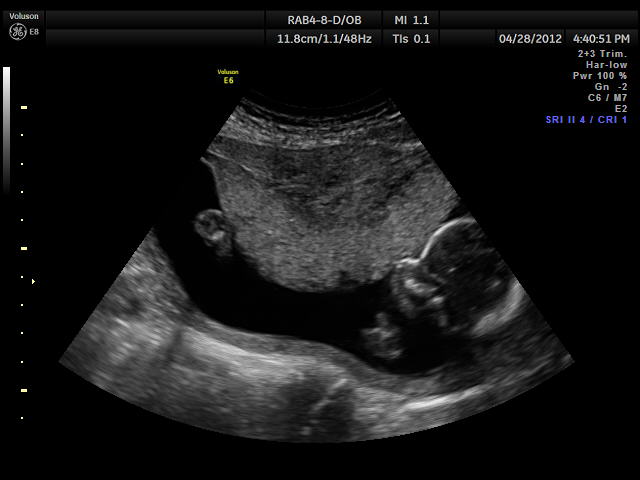

Now that I looked up a few pcitures... I say girl. #4 really looks like a girl to me and the skull.

Sorry to post so much... but I'm watching the U/S in slow-mo and just noticed "something" in b/w the legs. I dont know why SO MANY look like "girl"...

I still think girl on the basis of the very first pic which is the only one that really has a clear shot of the goods. If that's a penis in between the legs in the pic directly above, your son would have a great future as a porn star LOL!! That's either cord (looks too thick tho) or the baby had bent over a bit at the waist and it's spine.